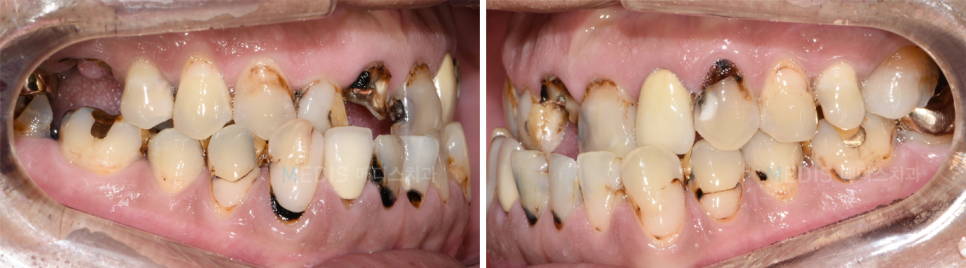

[디지털보철] 심한 치아우식 일반치료 및 임플란트 치료 후기

충치치료 + 임플란트 치료 전

※ 치료기간 : 2018.06.23~2018.12.22

(치료기간은 환자분의 협조도에 따라 달라질 수 있습니다)

※ 부작용 : 환자의 경향에 따라 통증, 부종과 멍 등의 부작용이 생길 수 있습니다.

* 상기 사진은 본원에서 치료를 받은 분의 동의를 얻은 사진으로 실제와 차이가 있을 수 있습니다.